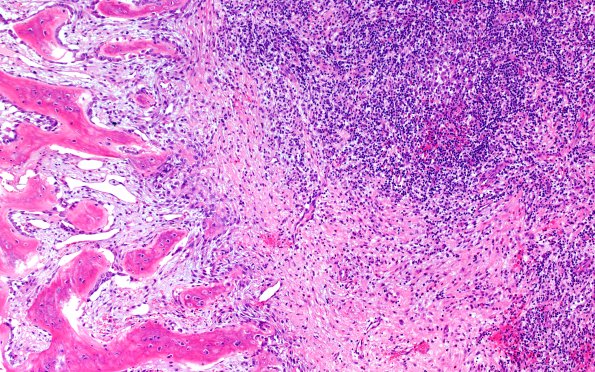

Washington University Experience | NEOPLASMS (HEMATOLYMPHOID) | Langerhans Cell Histiocytosis (LCH) | 24B2 LCH (Case 24) H&E 10X 3

H&E-stained sections show fragments of bone and soft tissue involved by a mixed chronic inflammatory cell infiltrate. (H&E)